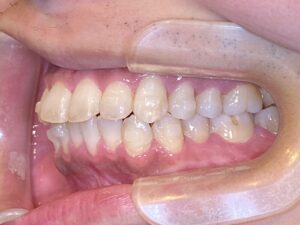

多数歯のIPRは噛み合わせを悪くする?虫歯リスクも上がるって本当?マウスピース矯正との関係も解説

矯正治療で歯の間を削る「IPR(Interproximal Reduction)」は、歯を抜かずにスペースをつくる便利な方法として注目されています。

しかし、多数歯に広範囲でIPRを行うと、噛み合わせが悪くなったり虫歯のリスクが高まることがあるのをご存じでしょうか?

IPRとは、歯と歯の間のエナメル質をごく薄く削ってスペースを作る処置のことです。

通常は0.1〜0.3mm程度を削りますが、多数の歯に対して広範囲に行う場合もあります。

この処置は、特に抜歯を避けたい非抜歯矯正や、マウスピース矯正でよく使われます。